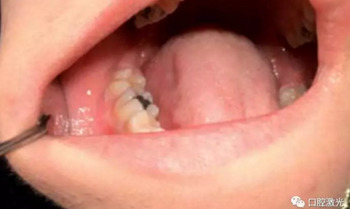

齦瘤指的是任何位于牙齦部的良性纖維瘤病變。齦瘤通常呈粉紅色,雖然為良性,但會(huì)隨牙齦一同生長,有時(shí)會(huì)因體積過大而包裹一顆或多顆牙齒。目前,齦瘤的具體病因上不可完全清楚,一般采用外科手術(shù)切除是被認(rèn)為是安全的,其中就包含利用口腔激光進(jìn)行切除。口腔激光擁有許多的波長,都可以用到齦瘤切除等軟組織手術(shù)中,并且擁有快速凝固和高效滅菌的特點(diǎn)。

本文收集了多位年齡在14至50歲的齦瘤患者,均活檢診斷后確認(rèn)。所有手術(shù)均在門診完成,全部使用半導(dǎo)體口腔激光。其功率設(shè)置為:4至6W,連續(xù)模式。光纖芯徑300微米。所有的患者都在術(shù)后1周,4周,6個(gè)月以及1年時(shí)間復(fù)診,評(píng)估激光手術(shù)的長期效果。

在治療前,患者、醫(yī)生及助手均佩戴正確的防護(hù)眼鏡,并且對(duì)患處進(jìn)行拍照記錄。隨后使用2%的利多卡因 1cc進(jìn)行浸潤麻醉。激光器設(shè)置完畢后,采取外切的手法,利用鑷子將齦瘤拉伸后,從其根部進(jìn)行外切。手術(shù)后無需縫針,并對(duì)切除物進(jìn)行病理學(xué)檢查。檢查結(jié)果確認(rèn)為纖維瘤。整個(gè)手術(shù)過程通常為4至6分鐘。建議患者術(shù)后冰敷以減少水腫發(fā)生。